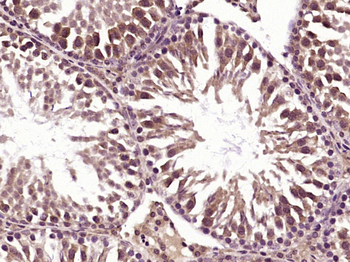

IF, IHC-Fr, IHC-P

应用稀释比例:IHC-P=1:100-500, IHC-F=1:100-500, IF=1:100-500